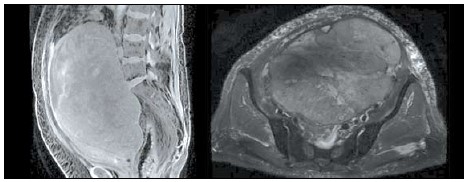

3. Рис. 3. МРТ: слева – Т2-режим; справа – Т1-режим. Примечание: рисунок выполнен авторами

Тема

Тип Исследовательские инструменты

Посмотреть (26KB)